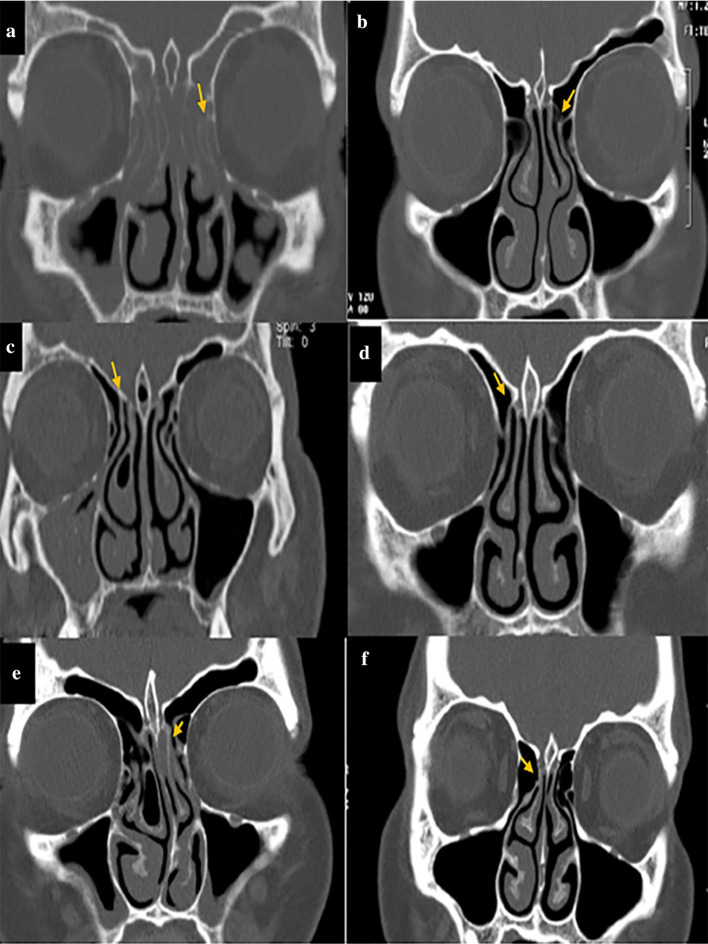

The angle formed between the line passing through the crista galli to the anterior nasal spine and the most prominent point of the deviated septum was considered as the angle of NSD (Fig. 2g, h). Also, according to a study by Orlandi et al. [19] who reported 10° septal deviation as the cutoff point, the obtained NSD values were categorized into two groups of NSD < 10°, and NSD ≥ 10°, and the two groups were compared in this respect. Moreover, the form of EI was divided into three types based on the attachment of the UP to lamina papyracea (type A), cribriform plate (base of skull) (type B), and middle concha (type C) as shown in Fig. 3. All CT scans were evaluated by a senior post-graduate student of oral and maxillofacial radiology under the supervision of an oral and maxillofacial radiologist.

Fig. 3.

Different forms of EI in patients with/without maxillary sinusitis; a, b Attachment to lamina papyracea (arrow); c, d: Attachment to the cribriform plate (base of skull) (arrow), e, f Attachment to middle concha (arrow)